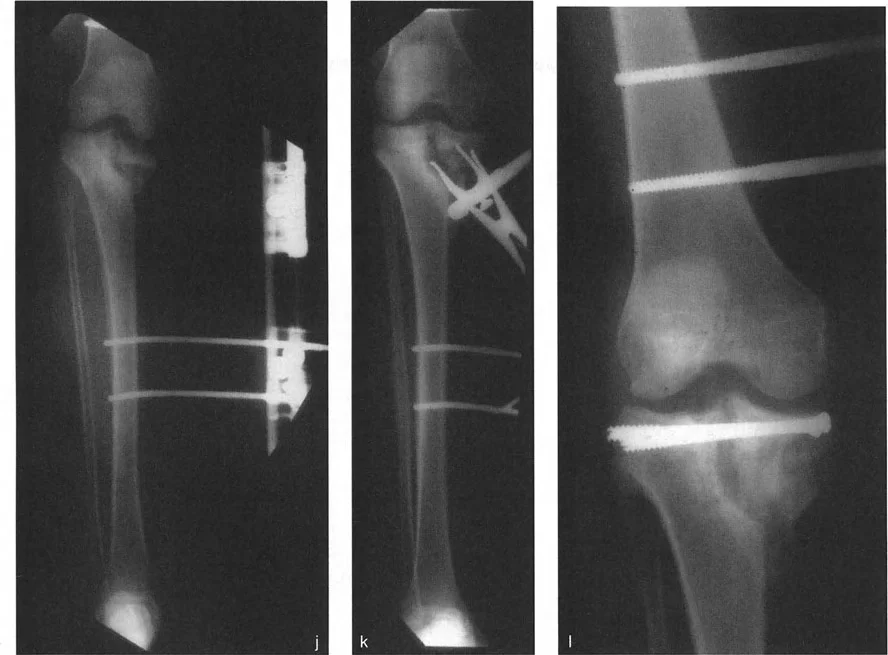

إعادة المحاذاة داخل المفصل رفع الهضبة

إذا قرر الجراح أن هندسة مفصل الركبة غير مقبولة - بسبب عدم استقرار سريري شديد، أو خلع متكرر، أو درجة كبيرة ستدمر الغضروف الهلالي والغضروف المفصلي حتماً - فيجب تحويل التخطيط والتنفيذ إلى تصحيح حقيقي داخل المفصل.

تسلسل التخطيط لرفع الهضبة

تتطلب جراحات قطع العظم داخل المفصل مهارة فنية عالية وتخطيطاً قبل الجراحة لا تشوبه شائبة.

- تحديد مستوى الهدف: ارسم خطاً يمتد من اللقمة أو الهضبة الطبيعية غير المنخفضة مباشرة نحو الجانب المنخفض. يصبح هذا الإ

التأثير الجراحي: بسبب هذا التسامح الهندسي، يمكن غالباً إعادة محاذاة سوء المحاذاة الناتج عن إزاحة لقمة الفخذ الأحادية أو سوء توجيهها باستخدام قطع عظم الفخذ فوق اللقمي خارج المفصل. لا تحتاج دائماً إلى تقسيم اللقم وإجراء عملية داخل المفصل عالية المخاطر. على النقيض من ذلك، فإن عدم الاستقرار الشديد الناتج عن درجات عظم الساق يتطلب دائماً تقريباً قطع عظم حقيقي داخل المفصل (رفع الهضبة) بدلاً من مجرد تصحيح في الميتافيزيس، لمنع التدمير السريع للمفصل.